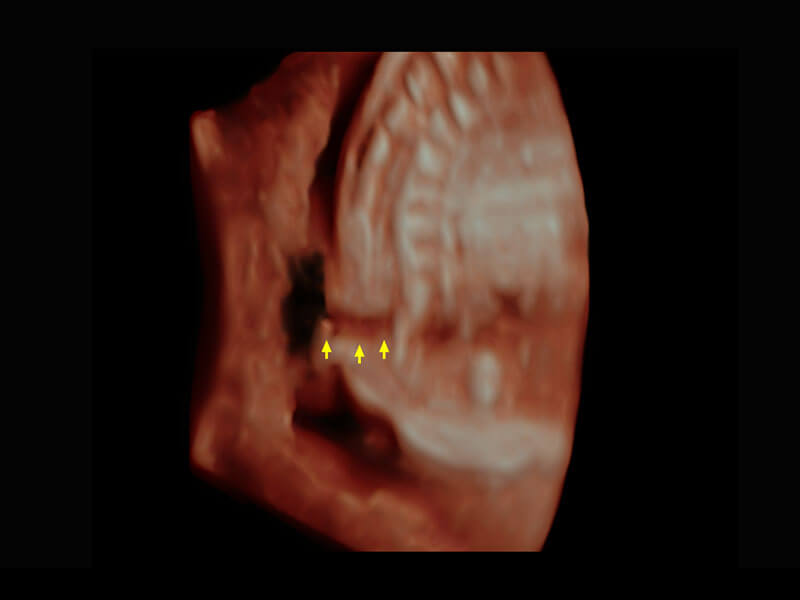

胎心筛查

P60搭载一系列胎儿心脏成像技术,实现精细的胎儿心脏评估。

• 四腔切面

• 四腔心血流